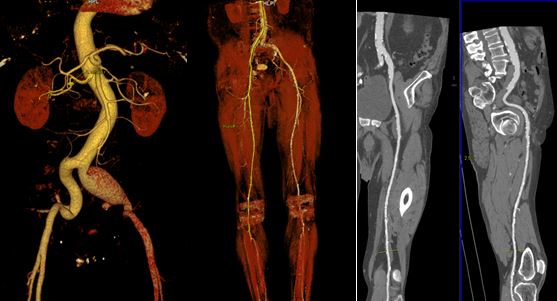

При отсутствии противопоказаний специалист выбирает один из двух видов ангиографии – артериальную или венозную. Выбор зависит от того, какие именно сосуды подлежат исследованию. В обоих случаях используются разные точки для прокола, через которые вводится контрастное вещество. Если врачу нужно уточнить ранее установленный диагноз, назначается КТ (компьютерная томография) ангиография сосудов нижних конечностей. Эта методика считается более эффективной и точной по сравнению с традиционной ангиографией.

Процедура включает в себя создание послойных изображений нижних конечностей. Затем формируется компьютерная 3D-модель, что позволяет врачу получить детальное представление о состоянии сосудов. Даже если потребуется сделать несколько снимков, доза излучения, которую получает пациент, значительно меньше, чем при использовании рентгеновского метода.

Компьютерная томография (КТ) с контрастированием также используется для визуализации сосудов. Этот метод позволяет получить высококачественные изображения и оценить состояние сосудов в трехмерном формате. Однако, КТ-ангиография требует введения контрастного вещества, что может вызвать аллергические реакции у некоторых пациентов. Кроме того, этот метод связан с облучением, что делает его менее предпочтительным для повторных исследований.